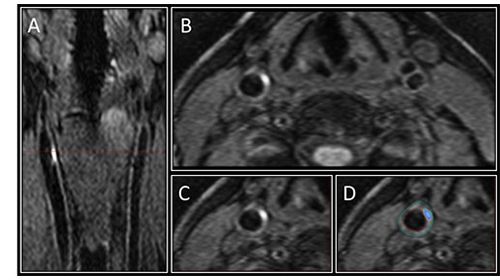

Case History: 60-year-old female with shortness of breath worsening with exertion and fatigue.

74-year-old with history of aortic valve repair at an outside hospital.